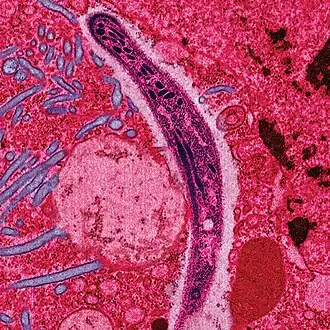

Malárie je způsobena Plasmodii (česky zimničky, parazitickými prvoky kmene Apicomplexa) a jejich přenašečem na člověka je komár rodu Anopheles. Jedná se tedy o zoonózu. Malárie napadá i jiné živočichy.[3]

Infikovaná samička komára Anopheles přenáší pohyblivé infekční stádium výtrusovce Plasmodium ve svých slinných žlázách. K infekci dochází většinou po setmění a v noci, kdy jsou samičky komárů nejaktivnější a sají krev teplokrevných živočichů. Zároveň se slinami přitom přenesou i Plasmodia (zimničky), které se poté uchytí v játrech infikovaného. V jaterních buňkách pak dochází k reprodukci parazitů a k přechodu do dalšího stádia – merozoitu. Merozoity vstupují do červených krvinek, kde se dále množí a v periodických intervalech dochází k jejich masovému uvolňování do krevního řečiště. Tomu odpovídají i typické malarické záchvaty, kdy dochází ke zvýšení teploty každé 3 nebo 4 dny, tj. v době, kdy je krev zaplavena čerstvou vlnou merozoitů.

Parazit je relativně chráněn před aktivitami imunitního systému, protože zůstává uvnitř jaterních buněk a krvinek. Cirkulující infikované krevní buňky jsou sice likvidovány ve slezině, ale plasmodium velmi rychle mění své povrchové proteiny, takže dokáže imunitní reakci účinně unikat. Když se časem lidský imunitní systém naučí rozeznat povrchový protein a začne produkovat specifické protilátky, parazit přepne do další formy proteinu a tím znesnadní práci imunitnímu systému.